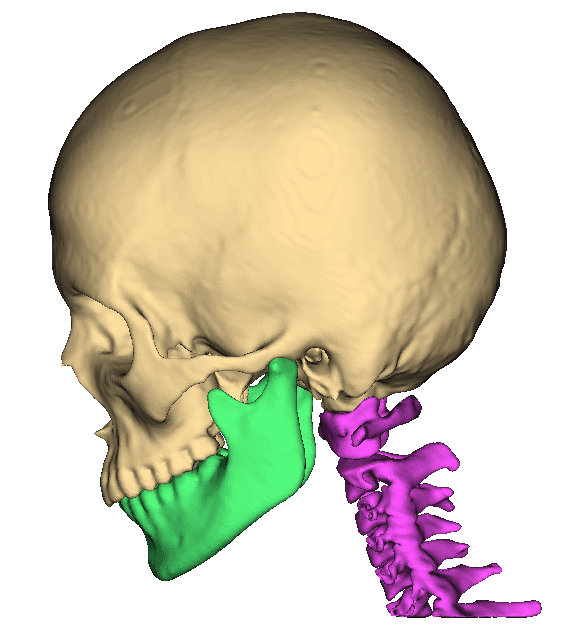

Segment bones, vasculature, and soft tissues with precision. User-friendly tools for accurate anatomical boundary delineation.

Real-time 3D rendering of segmented structures. Create patient-specific anatomical models for visualization and analysis.

Create patient-specific 3D anatomical models for pre-operative planning. Enhance surgical precision and patient outcomes.